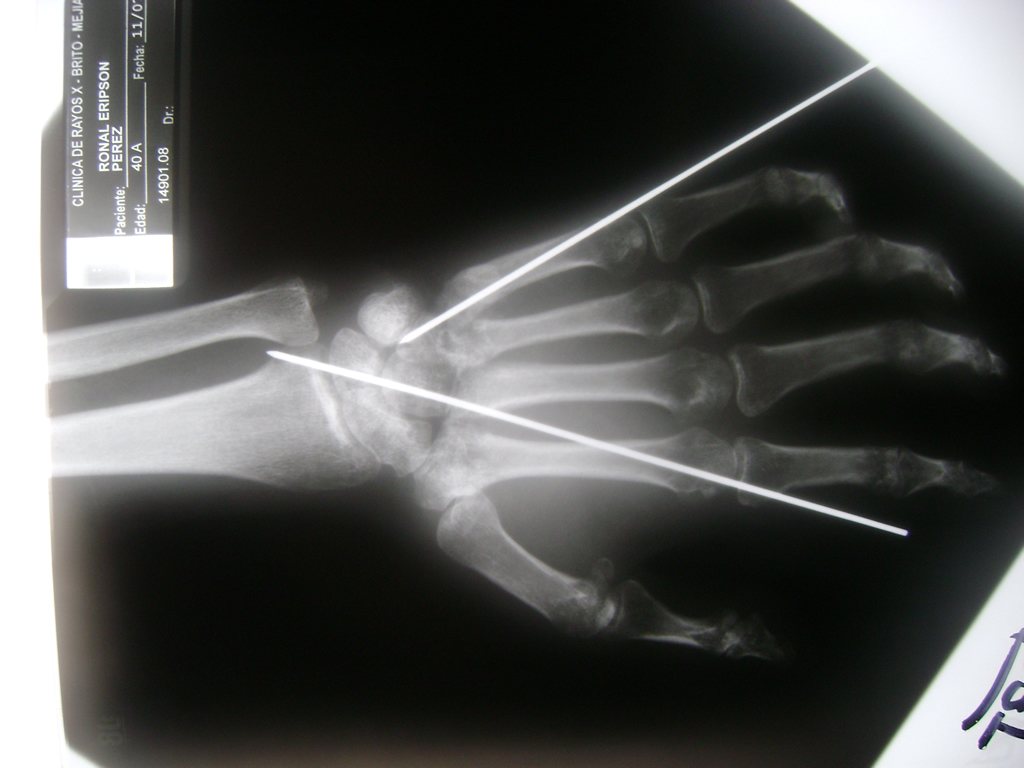

Cirugías de Calcaneo - Cirugías de Muñecas y Manos

Los procedimientos más comunes en cirugía de la mano son aquellos destinados a reparar traumatismos, incluyendo lesiones de tendones, nervios, vasos sanguíneos, y articulaciones; huesos fracturados; y quemaduras, cortes, y otros daños de la piel.